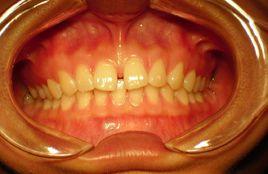

上唇系帶附著異常及其治療一直都是正畸學、牙周病學和口腔頜面外科學領域較為感興趣的研究方向。但至2018年關於上唇系帶方面的系統性文獻報導較少。上唇系帶是一帶狀的黏膜摺疊,連線了上頜骨牙槽突和中切牙的上唇黏膜。在出生時,上唇系帶通常較為明顯突出,隨著牙槽骨垂直向生長,系帶的附著向根尖方向移動並不斷縮小。若系帶的附著位置過於靠近牙齦緣,就形成了系帶的異常附著。這種解剖結構的異常可能是由於遺傳因素,也可能是由於牙周病或其他原因導致牙齦緣本身退縮至系帶附著的部位。。上唇系帶附著異常不僅會影響患

者牙齒和牙齦的美觀,而且可能會形成正中間隙而導致前牙咬合關係的異常,也會在一定程度上增加牙周病發生的可能性或加重原有的牙周病。

上唇系帶附著異常分類

在現有的文獻中,有學者根據形態學特徵提出了兩種上唇系帶異常的分類方法。Sewerin對1430例病例觀察分析後提出了一個早期的分類方法,主張將上唇系帶類型分為8類,即正常唇系帶、持續性頂唇系帶、附加物性唇系帶、結節性唇系帶、重唇系帶、凹陷性唇系帶、對裂唇系帶和符合以上兩個或兩個以上情況的唇系帶。根據此分類方法,Townsend等。對287例對象進行觀察統計,發現超過1/3的上唇系帶不符合正常唇系帶表型,其中最常見的變異表型為結節性唇系帶和附加物性唇系帶。1974年,Mirko等觀察分析了465例病例,基於上唇系帶和上頜中切牙的牙周組織特別是與牙周膜之間的相互關係,提出了一個分類方法,根據唇系帶附著位點的不同,分為4種類型:黏膜附著型、牙齦附著型、牙齦乳頭附著型和穿越牙齦乳頭附著型。